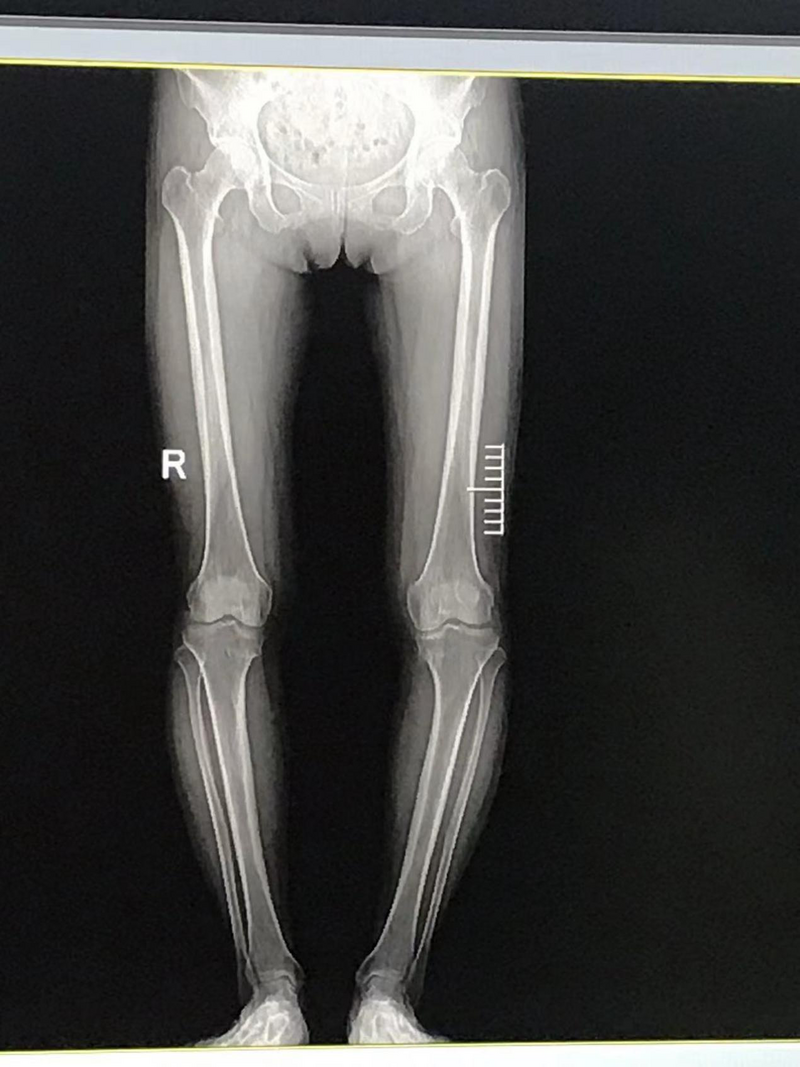

術(shù)前患者的雙膝內(nèi)翻畸形